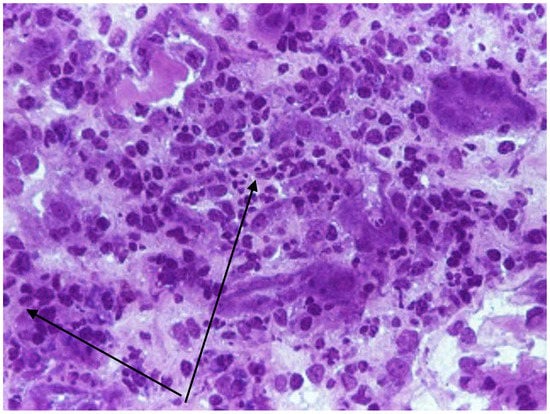

- Lupuşoru, G.; Lupuşoru, M.; Ailincăi, I.; Bernea, L.; Berechet, A.; Spătaru, R.; Ismail, G. Hanta Hemorrhagic Fever with Renal Syndrome: A Pathology in Whose Diagnosis Kidney Biopsy Plays a Major Role (Review). Exp. Ther. Med. 2021, 22, 984. [Google Scholar] [CrossRef]